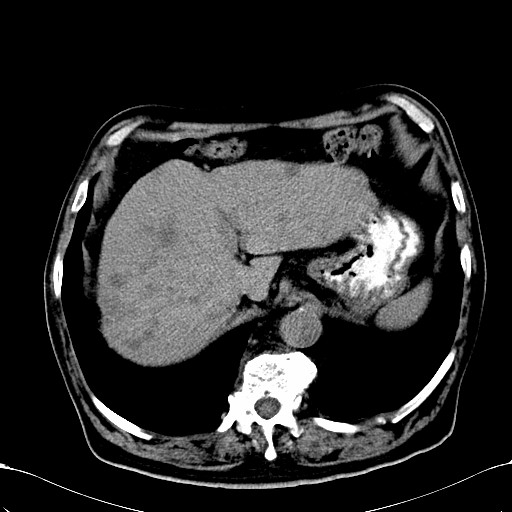

标题: CT28270:胰管扩张,肝多发占位 [打印本页]

标题: CT28270:胰管扩张,肝多发占位

患者,男,75岁。

考虑胰腺钩突癌并肝内转移,建议强化明确。

1)考虑胰头癌并肝脏多发性转移;建议行ct增强扫描检查。2)胃窦癌?建议行胃镜检查。

肝脏多方低密度结节,边缘模糊,考虑多发转移,胰管明显扩张,建议增强扫描钩突情况

肝脏多发低密度灶,胰头似呈低密度,胰管扩张,建议增强,

胰管显著扩张,但胆总管未见扩张征象,不太符合胰头占位!考虑慢性胰腺炎.胃窦占位并肝内转移可能!mrcp胃镜增强一起上!